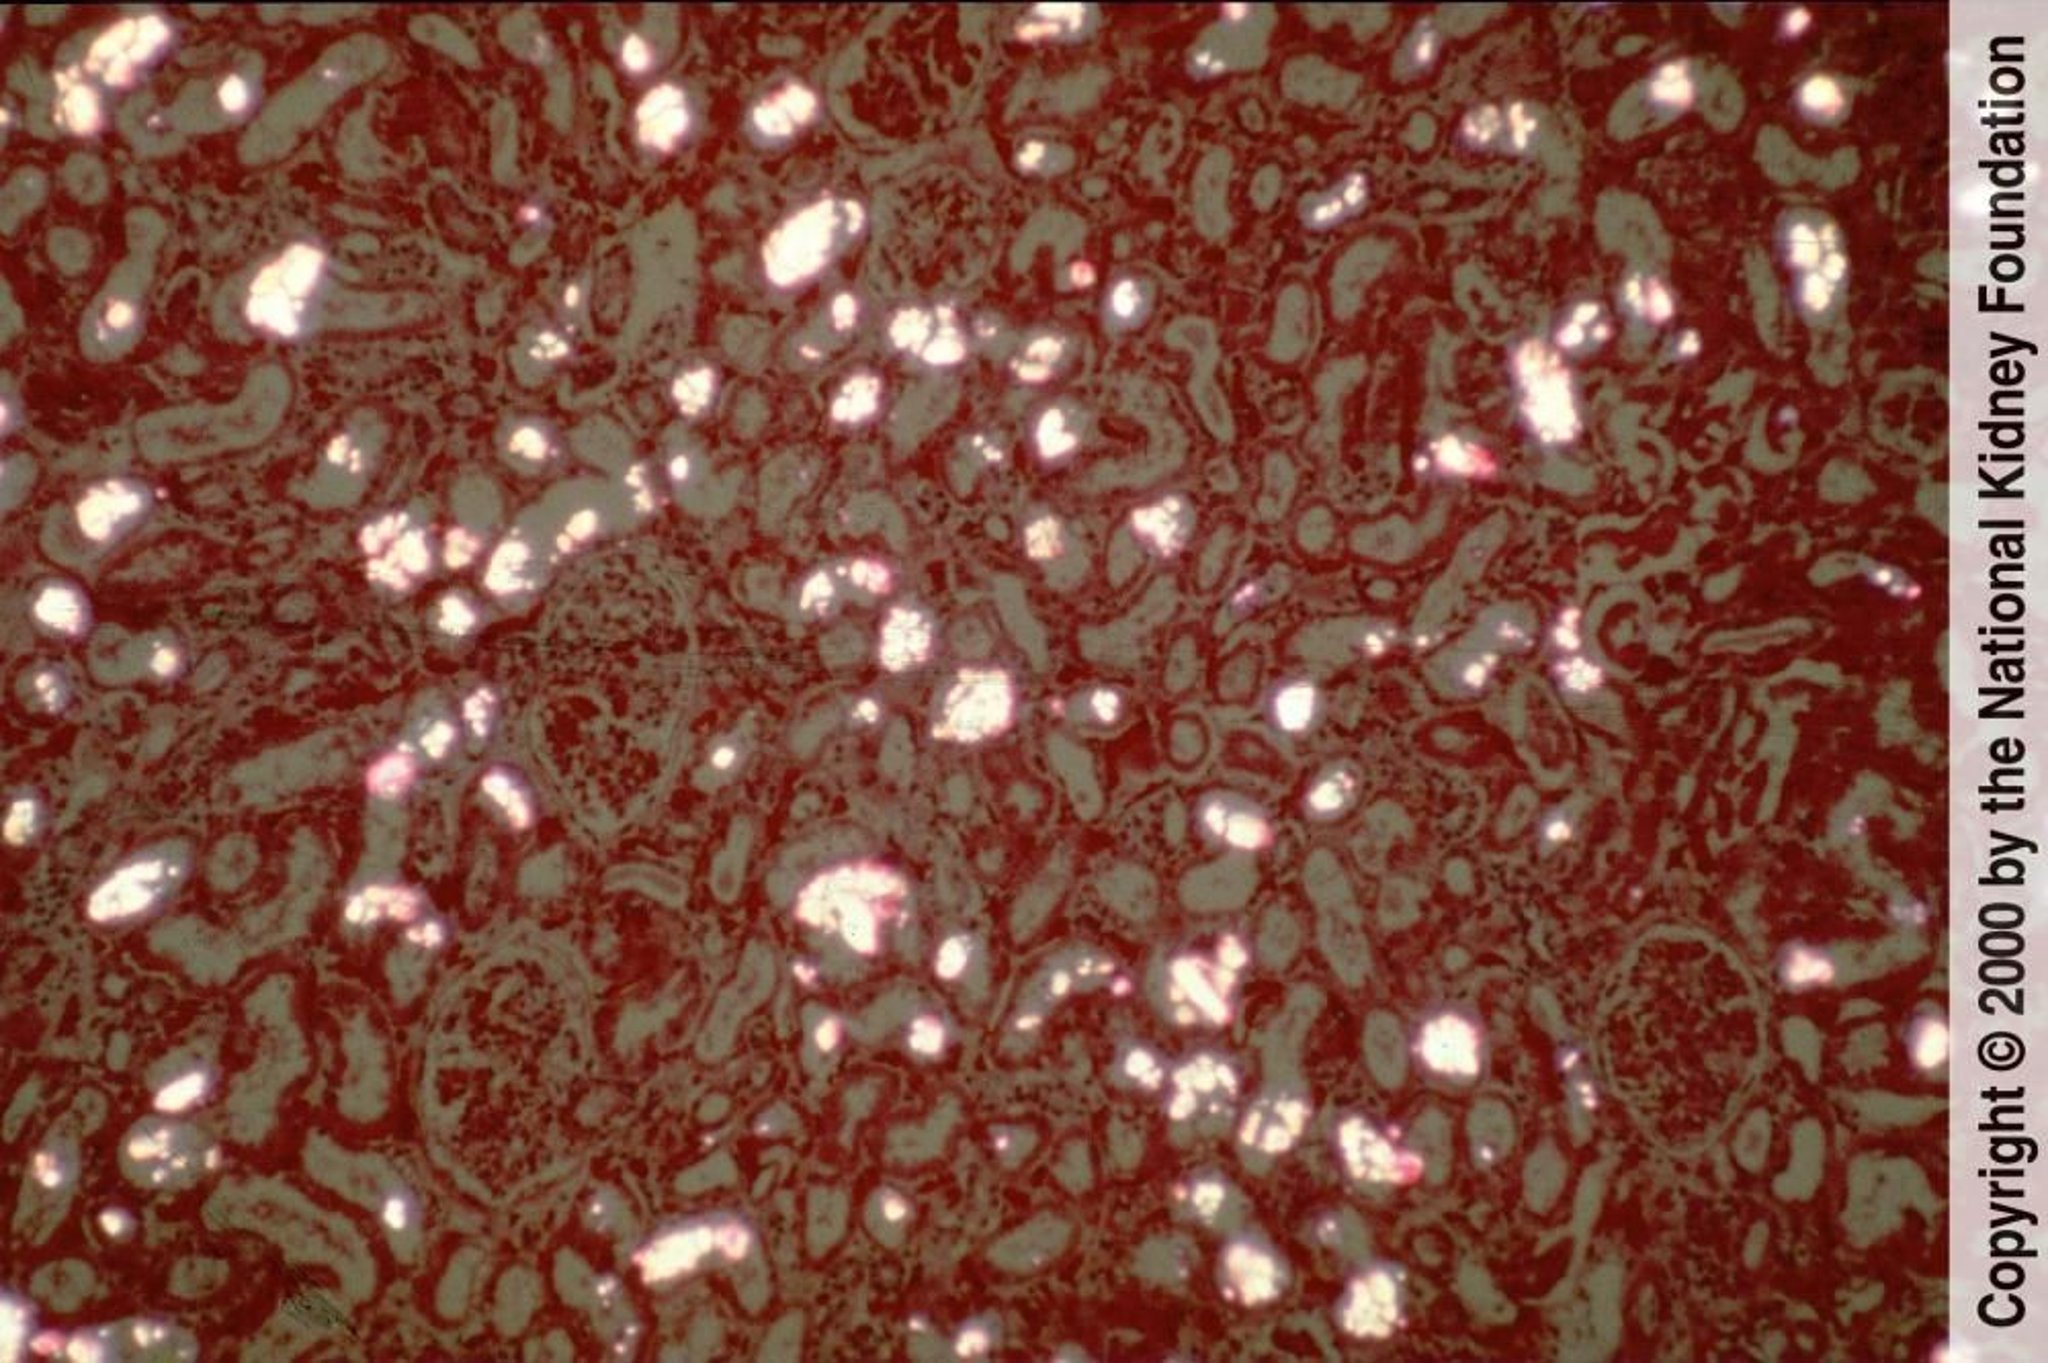

Os cristais de oxalato de cálcio se precipitam nos túbulos renais e são facilmente visíveis como cristais birrefringentes e em forma de leque ou feixe sob a luz polarizada (coloração hematoxilina-eosina polarizada, × 100).

Image provided by Agnes Fogo, MD, and the American Journal of Kidney Diseases' Atlas of Renal Pathology (see www.ajkd.org).